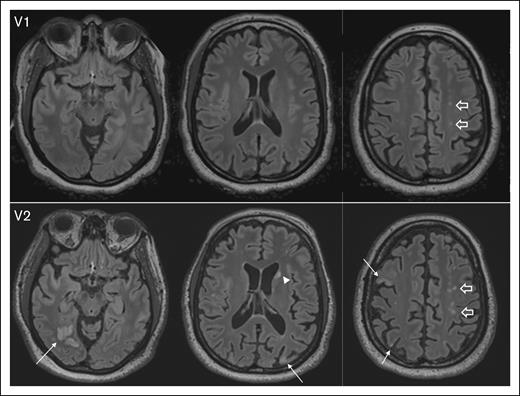

The median ARWMC score significantly increased from 3 (IQR, 0-7) at baseline (visit 1) to 4 (IQR, 1-7) at visit 2 (P = .002), suggesting ongoing cerebrovascular injury despite the absence of acute iTTP episodes. Representative MRI images illustrate the development of new lesions and the enlargement of existing SCI from visit 1 to visit 2 (Figure 2).

Figure 2.

Representative images depicting progression of SCI burden between V1 and visit 2 V2, with brain MRI completed 12 months apart. At V1, axial fluid-attenuated inversion recovery (FLAIR) images show several punctate foci of hyperintensity in the centrum semiovale (block arrows). At V2, there is interval development of multifocal chronic cortical infarcts; for example, in the right occipital, right and left parietal lobes, and right middle frontal gyrus (arrows), as well as an ischemic focus in the left caudate head (arrowhead). In addition, multifocal FLAIR hyperintense white matter lesions in the centrum semiovale bilaterally have increased in number and conspicuity (block arrows). V1, visit 1; V2, visit 2.